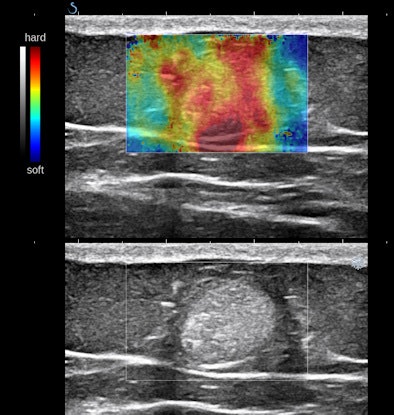

Some of you might think these nodules look like occasional findings in breast ultrasounds that are commonly thought to be lipomas. Lipomas are encapsulated fat, and they are distinguished from fat mainly by their capsular boundary. Here is another type of echogenic nodule, a solid mass of mixed histology with fat, muscle, and vascular components. This type of mass is typically palpable; their firmness is demonstrated by shear-wave elastography:

![]()  |

The first example is of an infiltrating, multifocal process, such as with leukemia; the second involves stable islands of cells without a supporting macrostructure; and the third is a solid, benign mass. The image features are distinct.